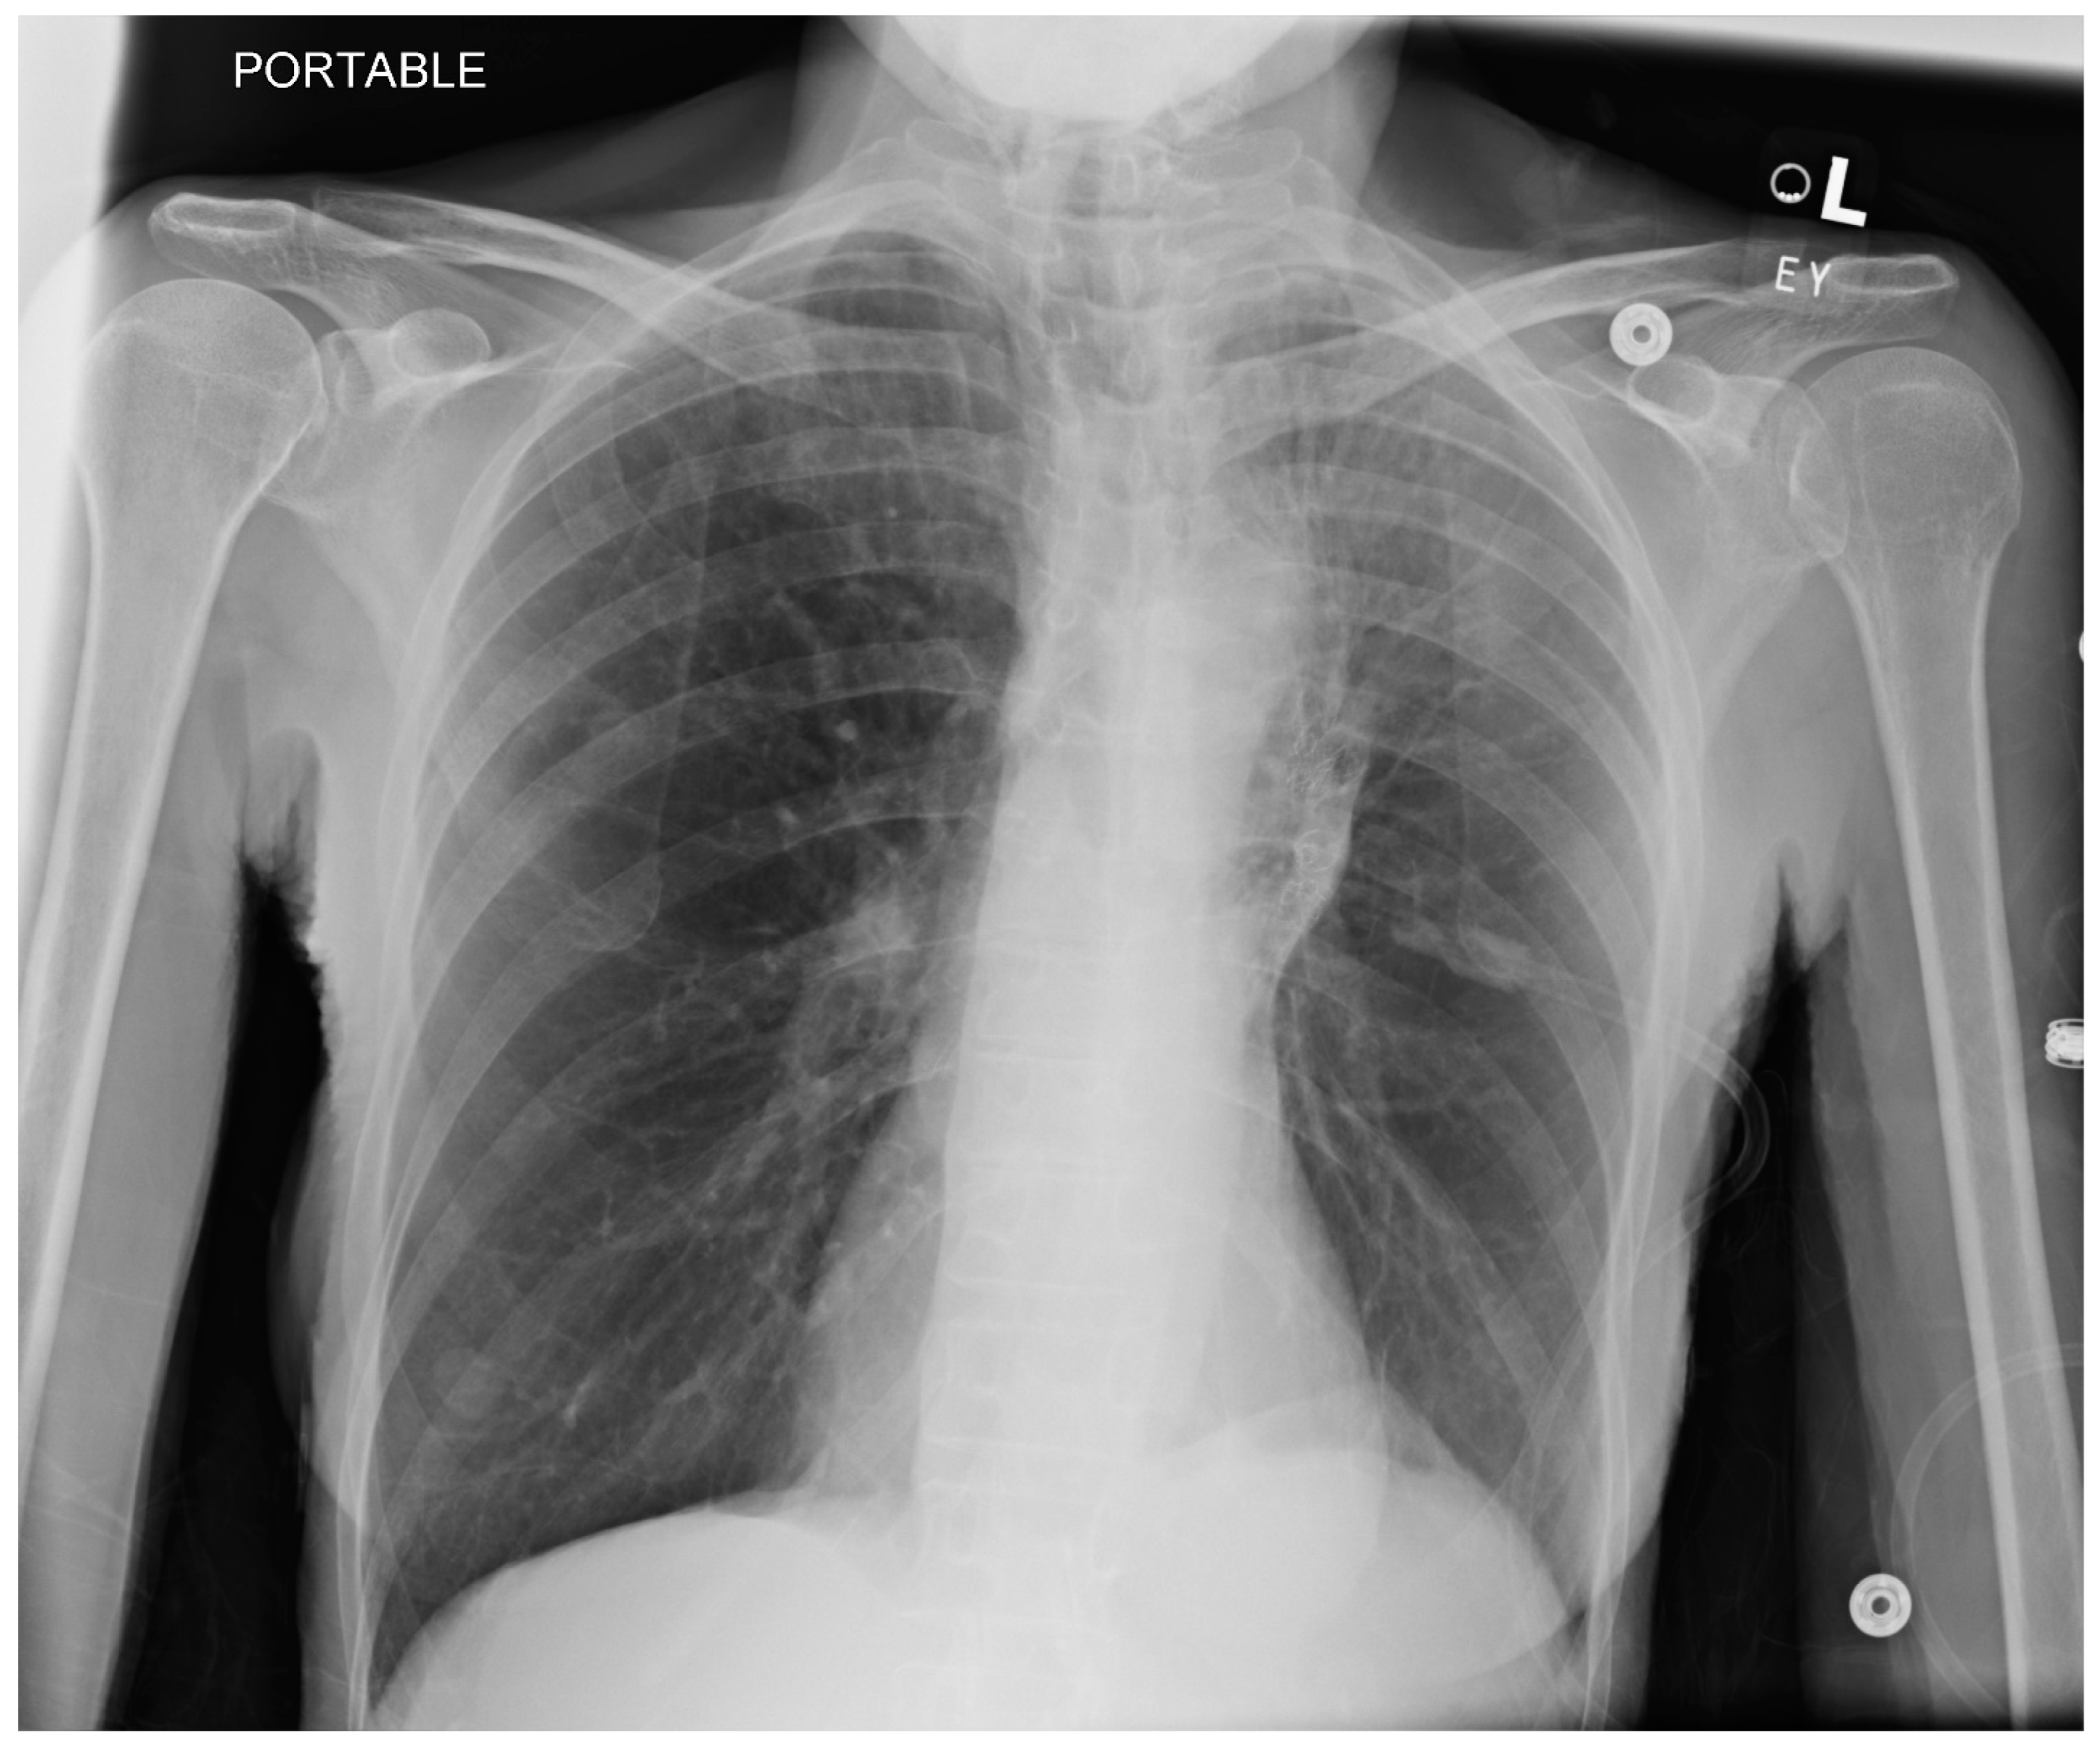

| Procedure | Indication and Preprocedural Factors | Anesthesia Requirements | Post-Procedure Factors |

|---|---|---|---|

| Navigational Bronchoscopy | Biopsying suspicious lesions. Patients are typically elderly with a history of smoking. | General anesthesia, usually TIVA with muscle relaxant. Larger than normal ETT (8.5) Avoid atelectasis without comprising safe oxygenation (SpO2 about 94%). Avoid 100% O2 even for induction. Air O2 mixture for maintenance. ETT position as guided by the bronchoscopist. Use appropriate ventilatory strategy to prevent atelectasis such as VESPA or LNVP (see text for details). Avoid barotrauma and hemodynamic instability during recruitment maneuvers. | Pneumothorax (3.4% to 9.8%). Respiratory failure and difficulty in extubation (rare). |

| Endobronchial valve placement | For lung volume reduction in selected cases of severe COPD | General anesthesia, TIVA with muscle relaxant. Larger than normal ETT (8.5) Hypotension to be expected and often requires phenylephrine support. | Pneumothorax is common, including tension pneumothorax. Incidence is reported as 4.2–34.4% (more often under GA than sedation). COPD exacerbation. |

| Bronchial thermoplasty | Indicated in selected patients with stable asthma without active respiratory tract infection. Should not have exacerbation of asthma for 2 weeks. Before BT, COPD to be excluded. Expect patients to have received steroids before procedure. | General anesthesia, glycopyrrolate for its antisialogogue properties, TIVA with muscle relaxant, ETT or an LMA. | Bronchospasm during or after bronchoscopy. Laryngospasm, atelectasis due to fibrin plugs. Exacerbation of asthma. Lower respiratory tract infections. Bronchial artery pseudoaneurysms. |